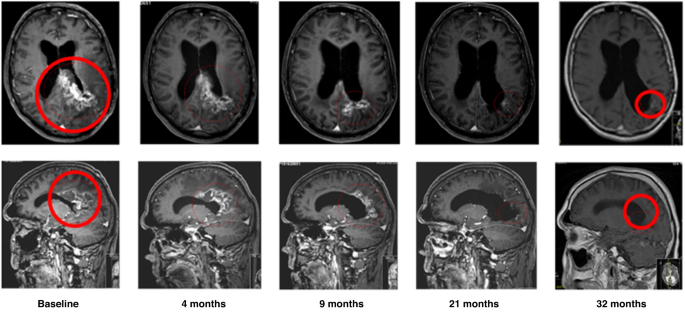

Twenty-one HGG patients had a radiological assessment at baseline and at least one post-baseline time point, so they were included in tumour response analysis. Eight of those 21 (38.1%) HGG patients had either a partial response (PR) or stable disease (SD) by RANO criteria (Fig. 3a and Supplemental Table 3). One patient (1/21) experienced a sustained PR of >2.5 years at 1000 mg daily between cycle 1 and cycle 44, and then at 12,000 mg daily between cycle 45 and cycle 48 (Fig. 4). Seven of the 21 patients (33.3%) had at least one report of stable disease, and four of these patients achieved SD for at least 6 months. All patients had received 2 or more lines of treatment without bevacizumab. Six patients had SD at doses of 12,000 mg daily or above. Eleven (52.4%) patients derived clinical benefit with either PR or SD as their best tumour response.

The patient showed a sustained tumour regression (partial response according to RANO criteria) over time for 3 years on monotherapy with 2-OHOA (500 mg BID, cohort 2). MRI transverse (upper scans) and sagittal (lower scans) brain images show the glioblastoma (red circle) reduction, which was determined to be ca. −93% of the initial volume.

2-OHOA monotherapy demonstrated promising anti-tumour activity, particularly in patients with HGG. Eight (38.1%) HGG patients experienced either a PR or SD by RANO criteria, with clinical benefit lasting at least 6 months in five patients. One patient with GBM who had been heavily pre-treated experienced a sustained partial response lasting for more than 3 years (Fig. 4). An encouraging 6-month PFS rate of 18.5% was observed in the relapsed glioma population. Activity in the other advanced solid tumours cohort was more modest, with clinical benefit lasting at least 3 months observed in three patients and a 6-month PFS rate of 3.7%.